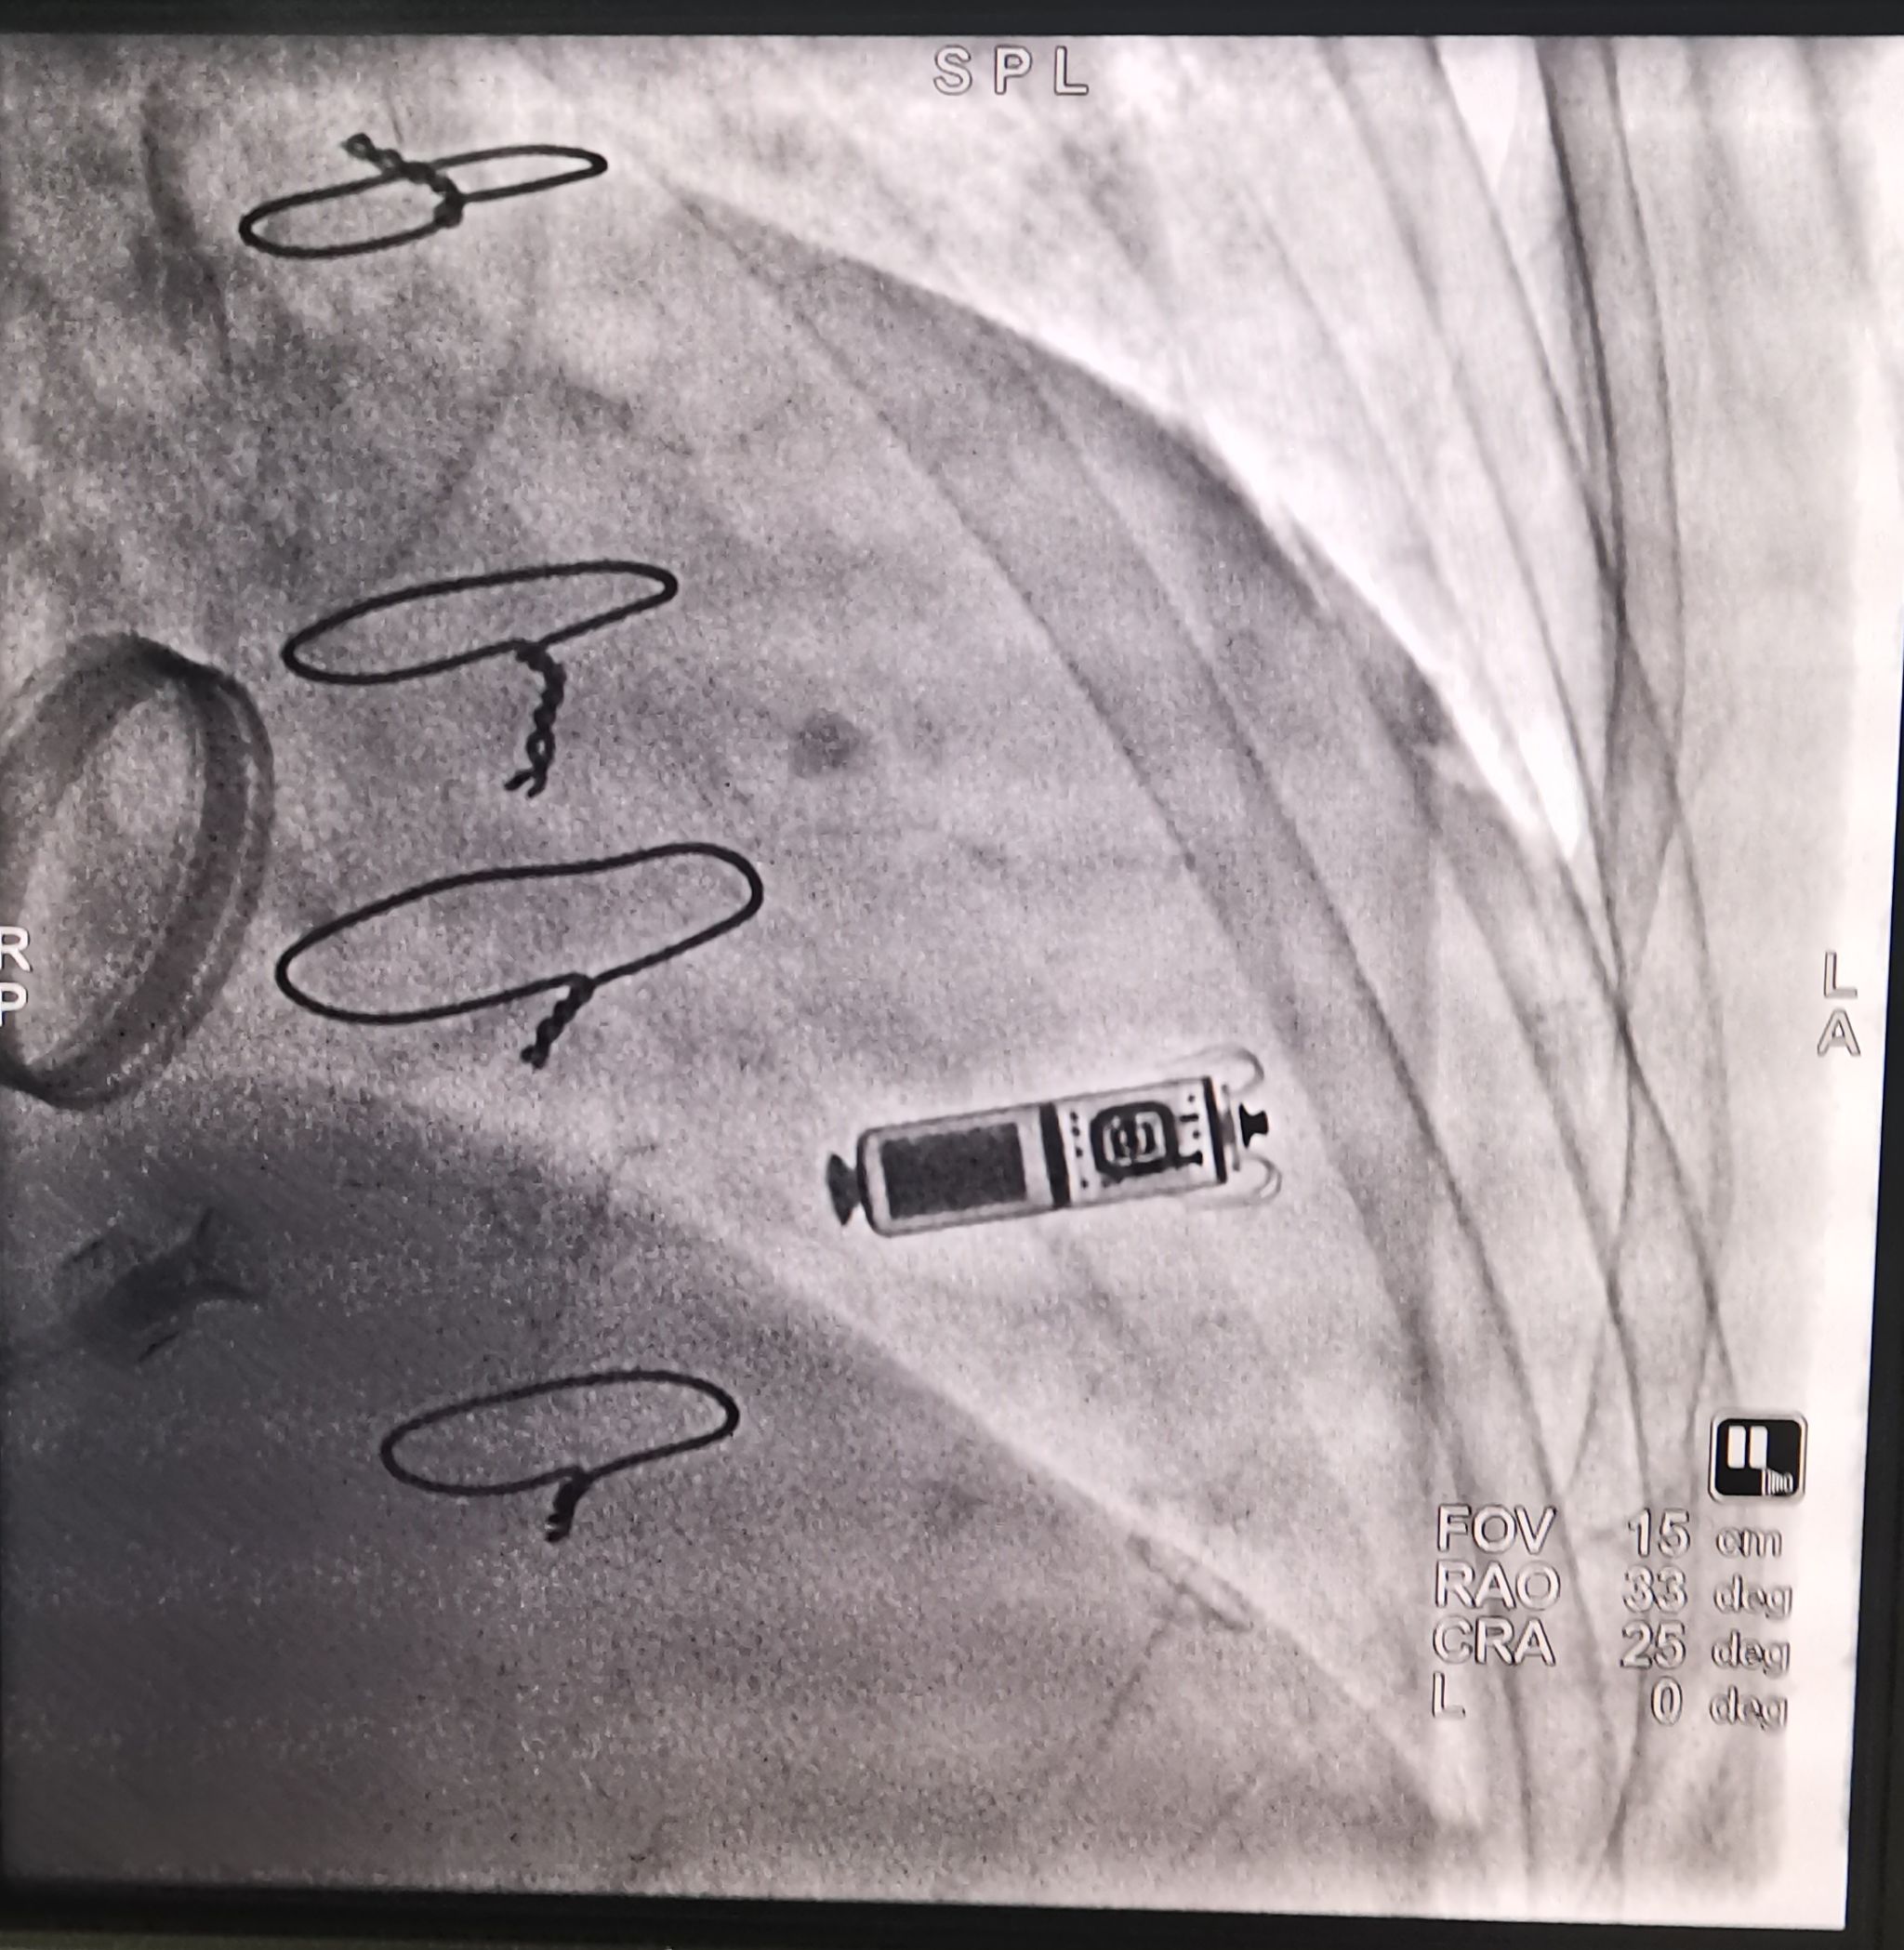

第二位患者是一名79岁高龄女性,风湿性心脏病20余年、二尖瓣机械瓣置换术后18年,房颤伴二度房室传导阻滞,最慢心率30余次/分,巨大左房(内径79mm),伴三尖瓣大量反流、肺动脉高压60mmHg。院外合并甲型H1N1病毒感染,入院查动脉血气:pH 7.38,PO243mmHg,PCO260mmHg,指脉氧饱和度85%,提示II型呼吸衰竭。医生予以抗病毒、抗菌素、呼吸机辅助通气、利尿、扩容等治疗后,心衰与呼吸衰竭得到纠正后,再次评估患者全身状态,考虑患者超高龄、体型瘦弱,传统有导线起搏器术中恐不能长时间平卧配合,术后囊袋及导线相关并发症风险较高,与家属反复沟通病情后,要求植入无导线起搏器。穿刺右侧股静脉送Micra递送系统经右心房跨三尖瓣送抵右室中位间隔区,造影见电极贴壁良好,原位释放起搏器,测试起搏参数:起搏阈值1.0 V,阻抗760Ω,感知5.0mV。行牵拉试验示起搏器固定良好,剪断栓绳后撤出输送鞘管,缝合伤口予以加压包扎。术程顺利,术后心电监护及程控起搏器工作良好。